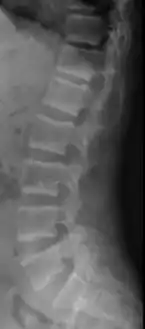

Renal osteodystrophy is usually diagnosed after treatment for end-stage kidney disease begins; however the CKD-MBD starts early in the course of CKD.[1][6] In advanced stages, blood tests will indicate decreased calcium and calcitriol (vitamin D) and increased phosphate, and parathyroid hormone levels. In earlier stages, serum calcium, phosphate levels are normal at the expense of high parathyroid hormone and fibroblast growth factor-23 levels. X-rays will also show bone features of renal osteodystrophy (subperiostic bone resorption, chondrocalcinosis at the knees and pubic symphysis, osteopenia and bone fractures) but may be difficult to differentiate from other conditions. Since the diagnosis of these bone abnormalities cannot be obtained correctly by current clinical, biochemical, and imaging methods (including measurement of bone-mineral density), bone biopsy has been, and still remains, the gold standard analysis for assessing the exact type of renal osteodystrophy.[6][15]